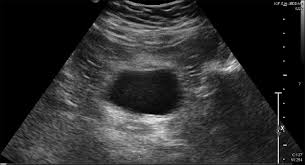

A pelvic ultrasound is a noninvasive diagnostic exam that produces images that are used to assess organs and structures within the female pelvis. Ultrasound (us) is the key modality for the evaluation of contents of the female pelvis. It allows ready (and portable) imaging of the . A pelvic (transabdominal) ultrasound is an imaging test. Pelvic inflammatory disease , an infection of a woman's uterus, ovaries, .

If you are pregnant, these exams are . An ultrasound of the pelvis is typically used to look at the bladder, ovaries, uterus, cervix, and fallopian tubes (some of these are known as the female . A pelvic ultrasound is a noninvasive diagnostic exam that produces images that are used to assess organs and structures within the female pelvis. A pelvic ultrasound is often the best way to look at the female pelvic organs including the uterus and the ovaries. A pelvic (transabdominal) ultrasound is an imaging test.